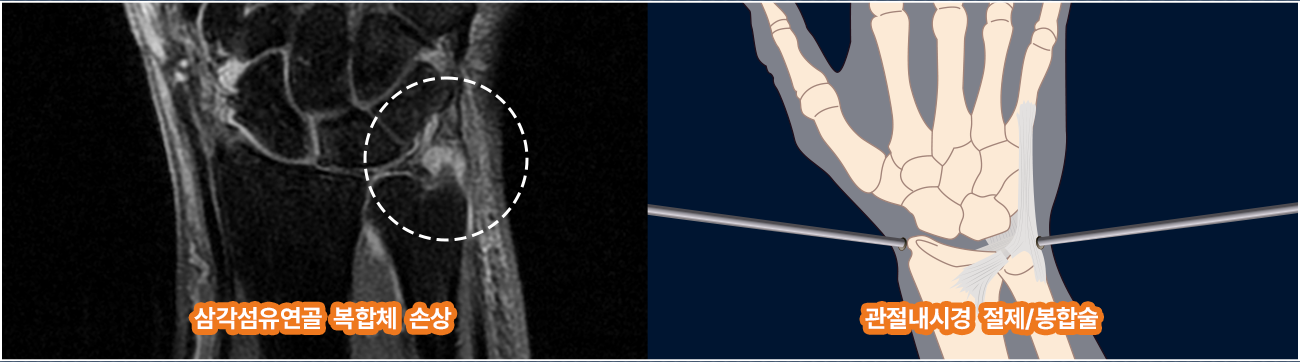

자기공명영상 검사 (MRI)

TFCC손상은 다른 질환에 비하여 방사선, 초음파검사만으로는 정확한 진단의 한계가 있기 때문에 MRI 검사를 통한 정확한 연부조직 손상의 확인이 필요합니다.

미세 관절내시경 변연절제,봉합술

관절내시경을 이용하여 피부 절개 없이 병변에 접근 후 염증을 제거해줍니다. 찢어짐이 있을 경우 수술 기구를 통해 주변을 다듬어주고, 찢어져 나풀거리는 부분은 손목을 움직일 때 뼈와 뼈사이에 찡기게 되어 통증을 느끼게 하는 원인이므로 역시 내시경 기구로 변연절제 해줍니다.

therapy therapy

벽쪽에 빨간 염증이 보이는 경우에도 내시경 절삭기로 전부 제거해줍니다. 절제된 부분은 레이저 기구를 이용하여 라이터로 지지듯이 열수축을 해서 찢어지지 않게 하며, 파열된 부분이 있다면 봉합술을 적용하여 마무리 합니다.